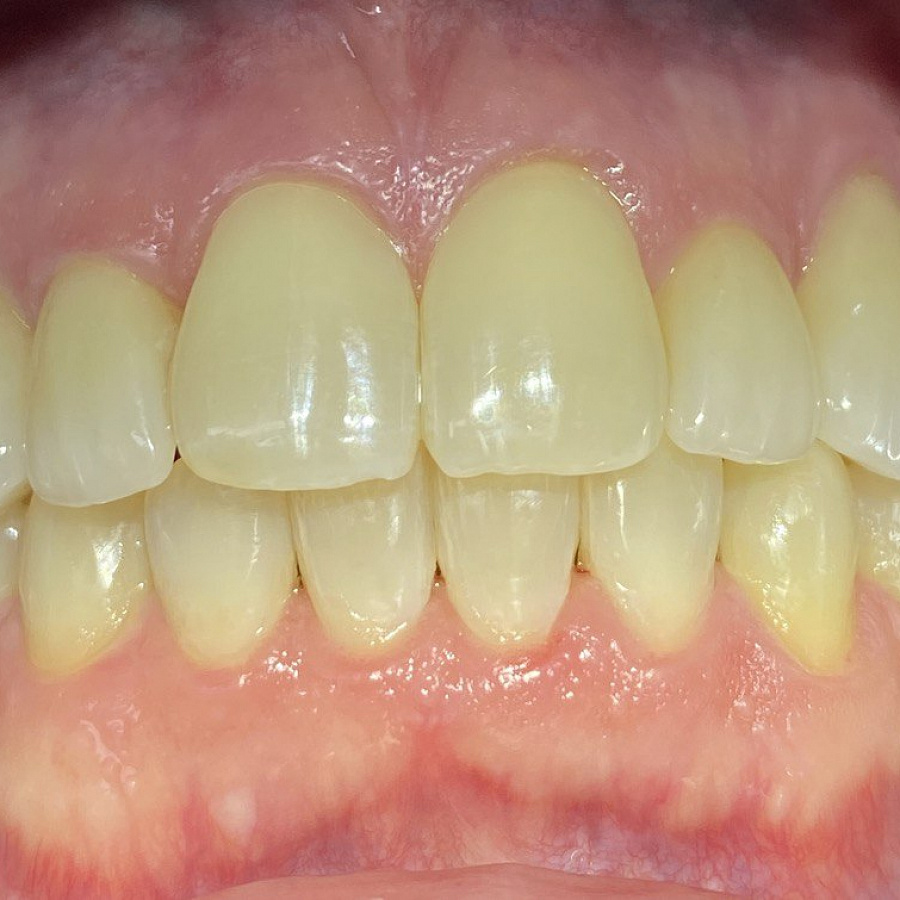

Результат лечения